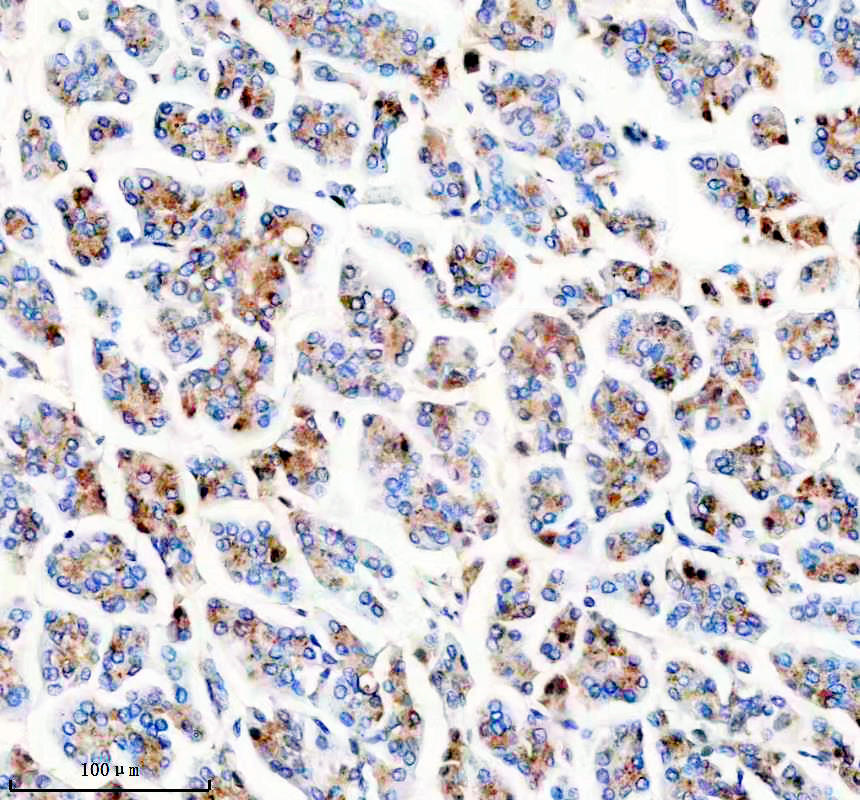

IHC analysis of Synaptophysin/SYP using anti-Synaptophysin/SYP antibody (BM4152).

Synaptophysin/SYP was detected in a paraffin-embedded section of human pancreas tissue. The tissue section was incubated with rabbit anti-Synaptophysin/SYP Antibody (BM4152) at a dilution of 1:200 and developed using HRP Conjugated Rabbit IgG Super Vision Assay Kit (Catalog # SV0002) with DAB (Catalog # AR1027) as the chromogen.